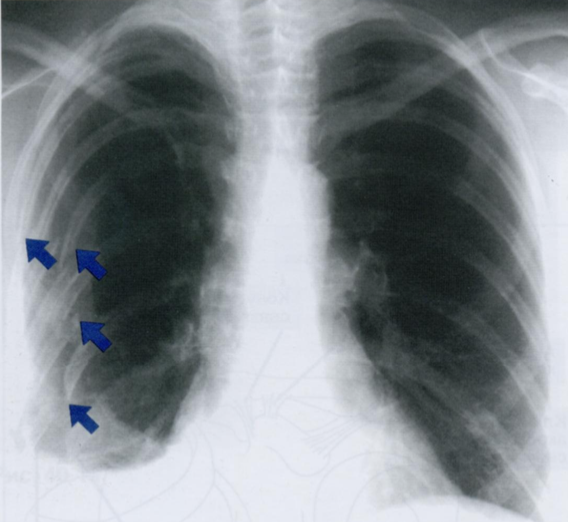

Перелом ребра на снимке выглядит как ступенька или прерывистость плотной кортикальной пластинки ребра.

Рентгенологический диагноз обычно не представляет затруднений (особенно с полными переломами и смещением костных отломков).